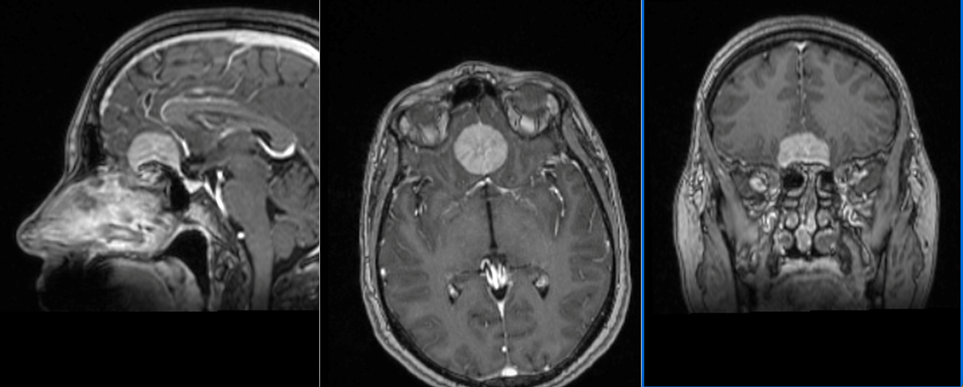

Pacientă tânără, în vârstă de 50 ani, diagnosticată în urmă cu 3 ani cu o tumoră de bază de craniu – etaj anterior, cu evoluție progresivă: de la 2 cm diametru în 2019 la 3 cm diametru în februarie 2023.

Tumora era bine delimitată, cu priză omogenă de contrast, și are origine din dura mater (foița externă a meningelui) de la nivelul șanțurilor olfactive – porțiunea din baza craniului pe unde trec nervii olfactivi. Aspectul RMN sugerează un diagnostic histopatologic de meningiom – tumoră benignă (în peste 95% din cazuri) .

RMN cerebral de control efectuat a doua zi după operație confirmă rezecția completă a tumorii și absența oricăror complicații.